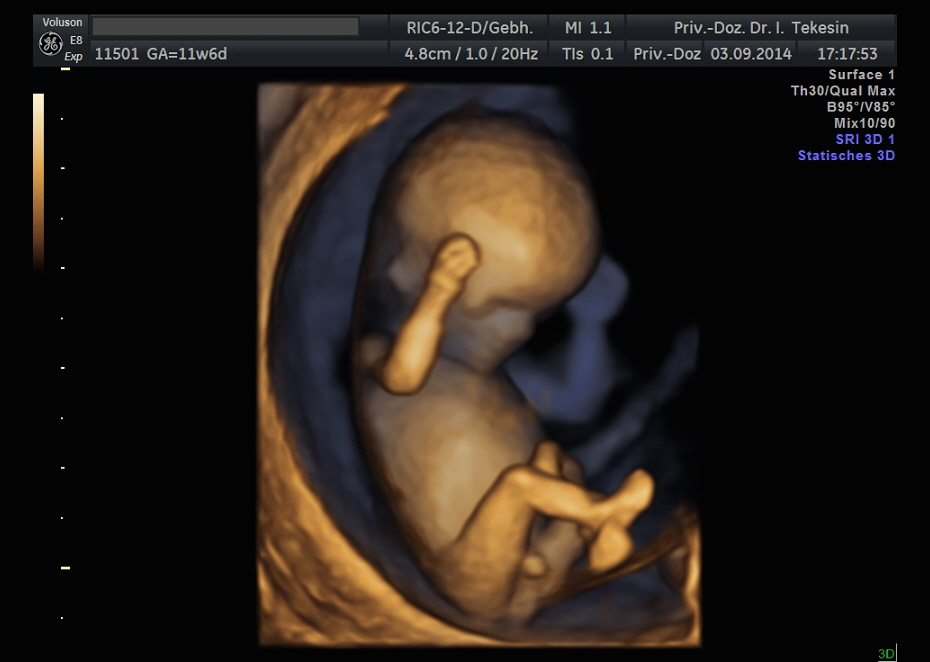

3D-/4D-Ultraschall (optional)

Immer mehr werdende Eltern interessieren sich für die faszinierenden Bilder, die dieses Verfahren liefert. Die plastische, dreidimensionale Darstellung der Oberfläche des Gesichts und anderer Körperregionen wird durch spezielle Bildrekonstruktion in schnellen Rechnern erreicht. Auch einzelne innere Organe oder „Gefäßbäume“ können von allen Seiten betrachtet werden. Viele dünne Schnittebenen (2D) werden zu einer gemeinsamen 3D-Sichtweise im Computer des Ultraschallgerätes zusammengeführt. Unter einem 4D-Ultraschall versteht man darüber hinaus eine 3D-Ultraschalluntersuchung unter Echtzeitbedingungen. Anstatt nur statische Bilder anzuzeigen, erfasst ein 4D-Ultraschall die Bewegungen des Kindes, weshalb er auch als „Live-3D-Ultraschall“ bezeichnet wird.

Diese Vorgehensweise ermöglicht äußerst realistische Bilder, bei denen sogar Gestik und Mimik des Kindes in bewegten Sequenzen festgehalten werden können. Die Untersuchung kann wie auch der normale Ultraschall während des gesamten Schwangerschaftszeitraums durchgeführt werden. Möchte man das Ungeborene komplett sehen, wird die 12. bis 16. Schwangerschaftswoche empfohlen, die Zeit zwischen der 28. und 33. Schwangerschaftswoche eignet sich besonders zur präzisen Darstellung einzelner Körperteile

Wir sehen in diesem modernen Verfahren in erster Linie eine ergänzende Maßnahme bei speziellen Fragestellungen bezüglich Herz, Gehirn oder Skelett und vor allem bei Verdacht auf eine fetale Besonderheit.

Kind in der 12. Woche

Kind in der 12. Woche (3D-Darstellung)